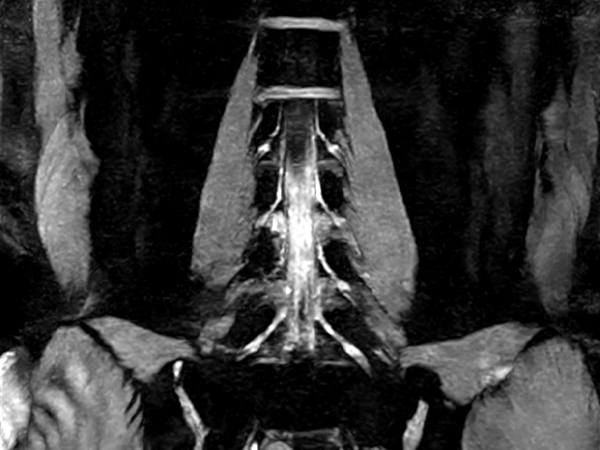

Coronal 3D WATS